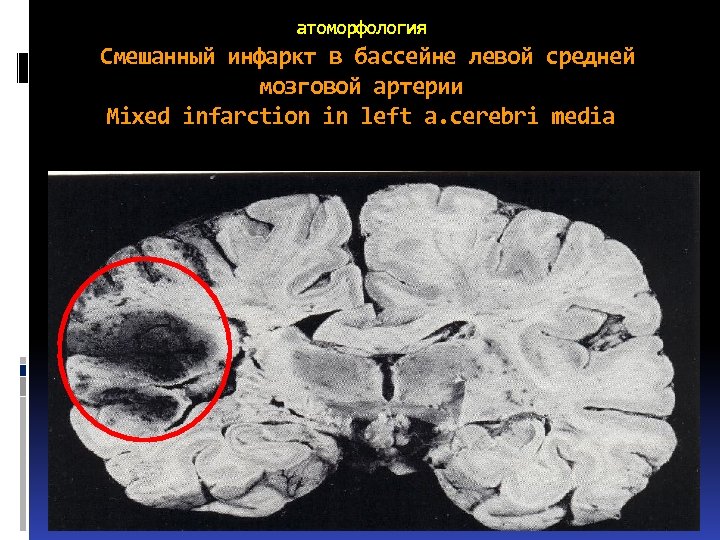

Патоморфология Смешанные инфаркты такие, которые на одних участках являются белыми (серыми), на других – красными.

Патоморфология Смешанные инфаркты такие, которые на одних участках являются белыми (серыми), на других – красными.

атоморфология Смешанный инфаркт в бассейне левой средней мозговой артерии Mixed infarction in left a. cerebri media

атоморфология Смешанный инфаркт в бассейне левой средней мозговой артерии Mixed infarction in left a. cerebri media